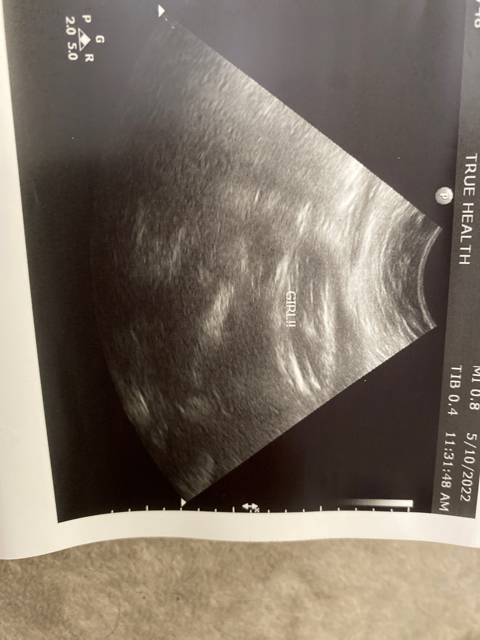

Ultrasound pics🫶🏼✨

Finally was able to see my baby girl 🥹💛 these are not good pictures but I was able to see her actual face during my ultrasound session. I am currently 33 weeks and She is 4.36 lbs and 17inch🫢 I pray everyday for her growth and wellbeing while being inside the womb. She is so strong 💕